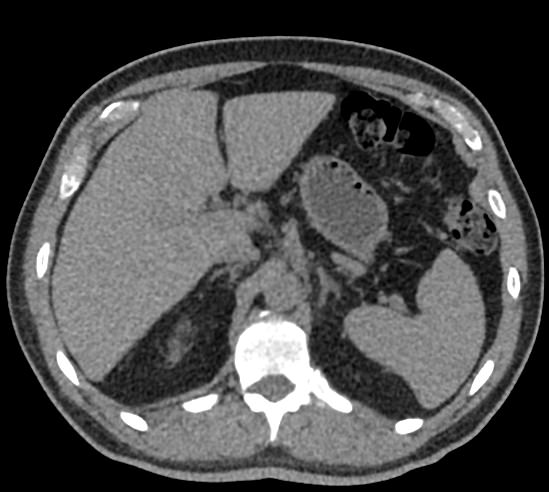

Одним из наиболее информативных методов диагностики заболеваний надпочечников является мультиспиральная компьютерная томография. МСКТ надпочечников относится к лучевым методам исследования, то есть для получения послойного изображения структуры органа используется проникающая способность рентгеновских лучей.

В клинике «Доступная медицина» мультиспиральная КТ надпочечников выполняется на современном 128-срезовом томографе экспертного класса TOSHIBA AQUILION CXL, который производит множество послойных снимков за несколько секунд. Быстрота исследования обеспечивает пониженный уровень лучевой нагрузки на пациента, а благодаря инновационным компьютерным программам томограф создает трехмерные модели органа, позволяющие оценить структуру надпочечников и окружающие ткани.

Кроме нативной компьютерной томографии МСКТ надпочечников проводится с применением рентгеноконтрастного вещества на основе йода. Контраст вводится пациенту внутривенно и усиливает визуализацию новообразований на фоне неизмененных тканей.

Контрастирование позволяет, в первую очередь, обнаружить опухоли минимальных размеров, что особенно важно при онкологических процессах для назначения своевременного лечения.